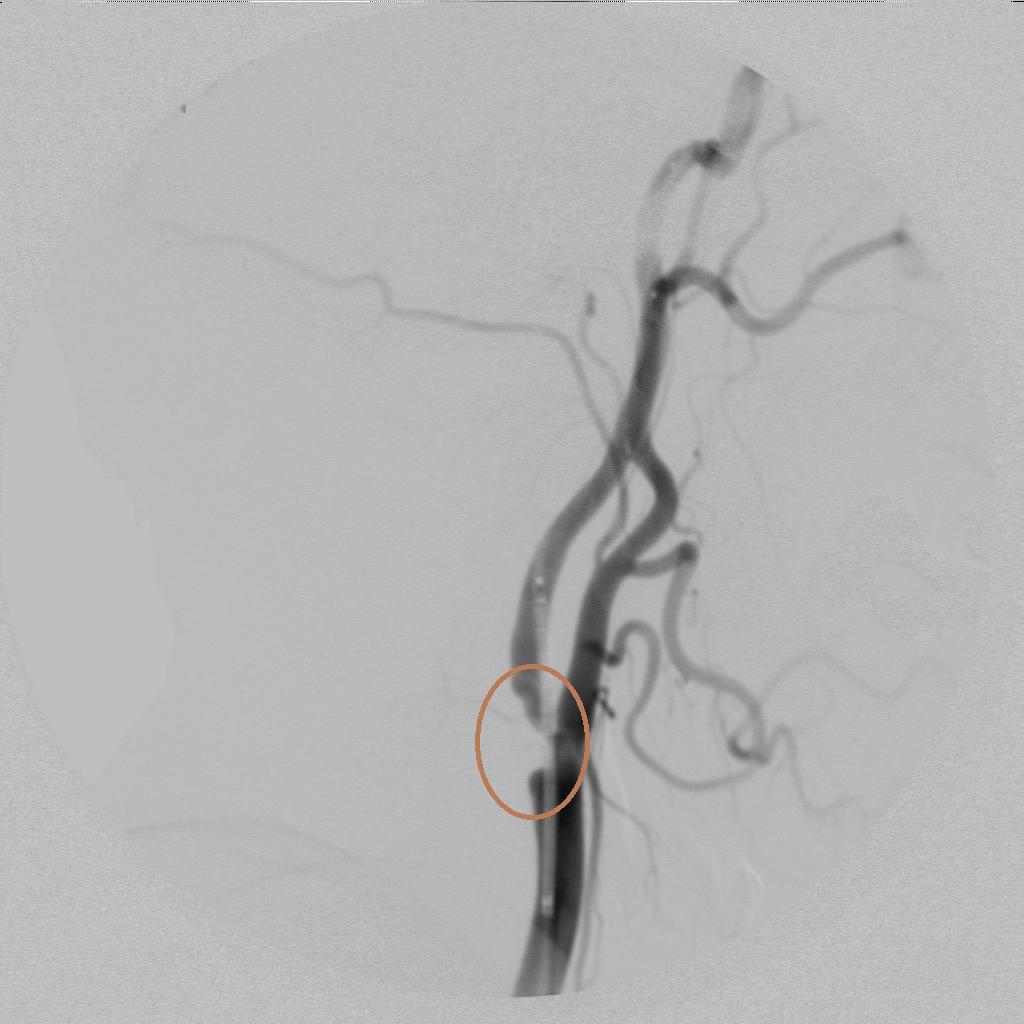

脑血管造影术发现右侧颈内动脉起始部狭窄!

术中进行血管再通治疗